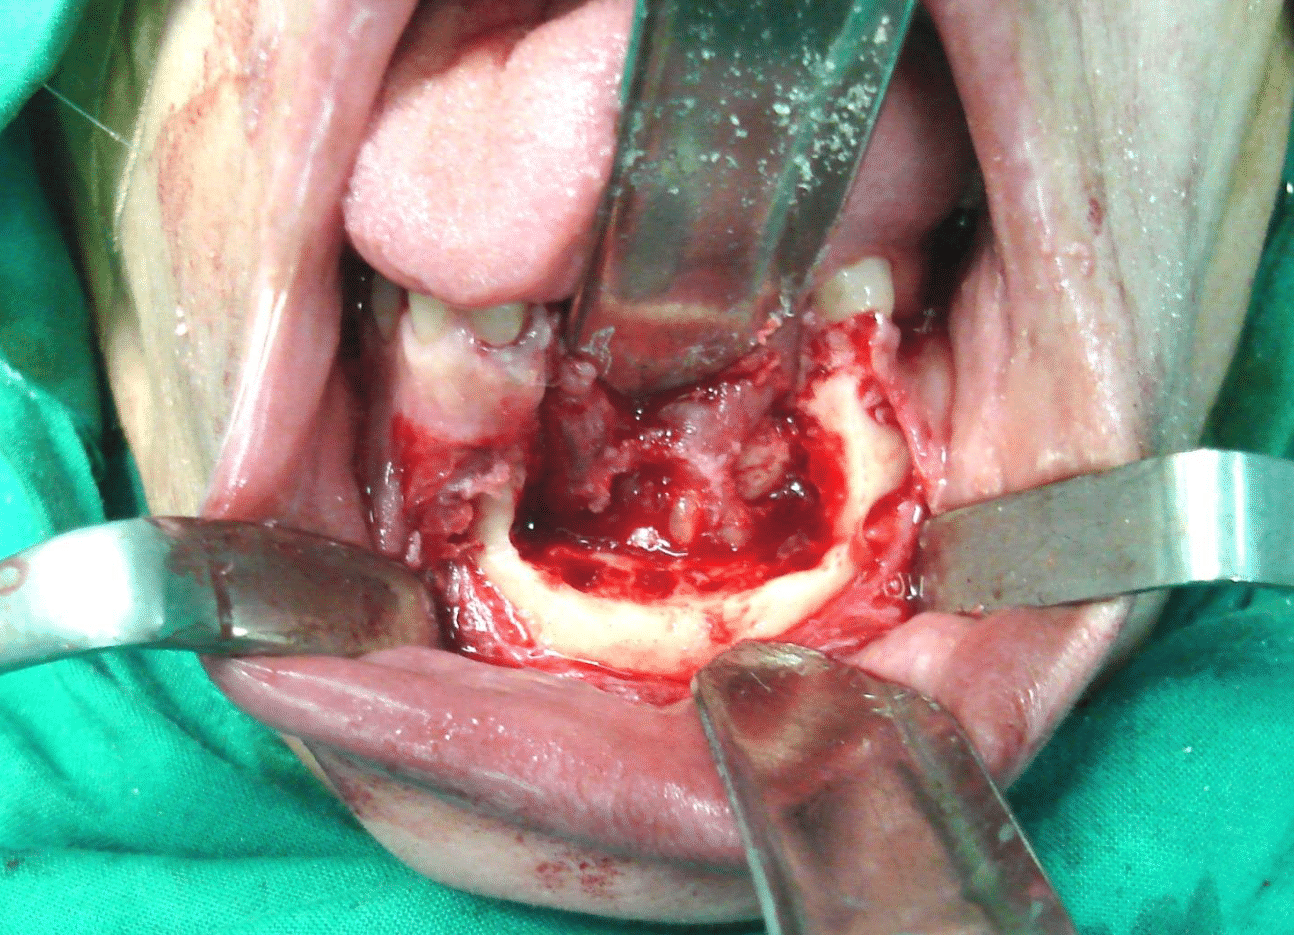

IRB and patient informed consent were obtained. Under general anaesthesia, marginal mandibular resection (alveolar rim resection with preservation of the inferior border) was done with safety margins around all the tissues with clinically evident tumor including the teeth. The safety margin involved the right central and lateral incisors and left canine and first premolar teeth with 0.5 cm of the bone apical to the teeth. A thin osteotome is then used to complete the bony cut through the alveolar process and between the teeth, attempting to maintain the integrity of the soft tissue and avoid damaging teeth. The wound healing was decent, and the soft tissue profile was good (Figure 3A, B, C, and D).

Figure 3a Outline of the mandibular marginal resection with surgical burs.

Figure 3b The resected bony segment.

Figure 3c The mandible after resection of the GSCC.